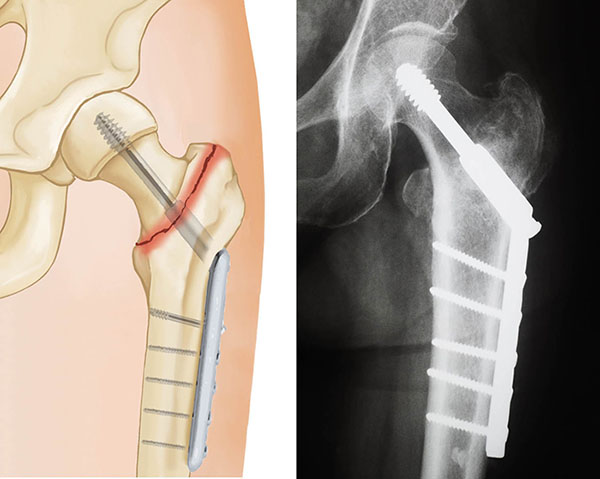

Subtrochanteric Fracture

Subtrochanteric fractures involve the upper part of the shaft of the femur, just below the hip joint.

They are treated surgically with an intramedullary nail into the shaft of the femur and a screw placed through the nail into the femoral head.

To keep the bones from rotating around the nail or from shortening (telescoping) on the nail, additional screws may be placed at the lower end of the nail near the knee. These are called interlocking screws.

In some cases, your surgeon may choose to use a compression screw with a long side plate instead of a nail.

treatment options for subtrochanteric fracture

X-rays show treatment options for a subtrochanteric fracture: (Left) Intramedullary nail and screw, (Center) An interlocking screw has been placed at the lower end of the femur to prevent the bone from shortening. (Right) Side plate and compression screws.